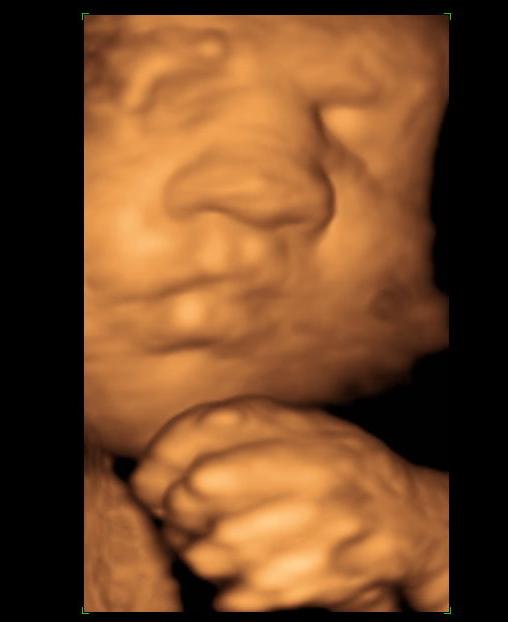

I posted my ultrasound pics from my 12 week 4 day scan previously and I just got back from my 18 week 1 day paid Gender Scan :)

Let me know what you think :)